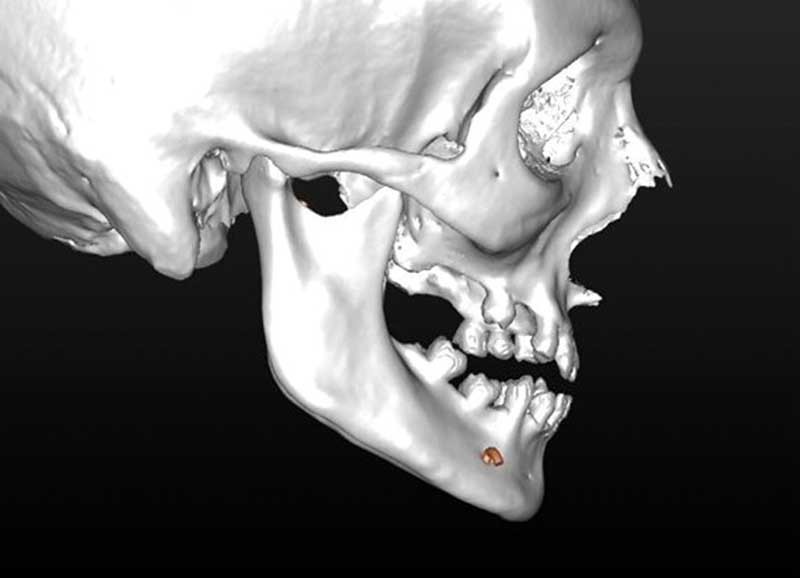

Les données natives en format DICOM sont ensuite traitées (phase de segmentation) :

– suppression des artefacts ;

– élaboration des images 3D en isolant des différents constituants anatomiques : crâne et maxillaire, mandibule, dents, dispositifs d’orthodontie, implants endo-osseux et prothèses conjointes éventuelles, etc.